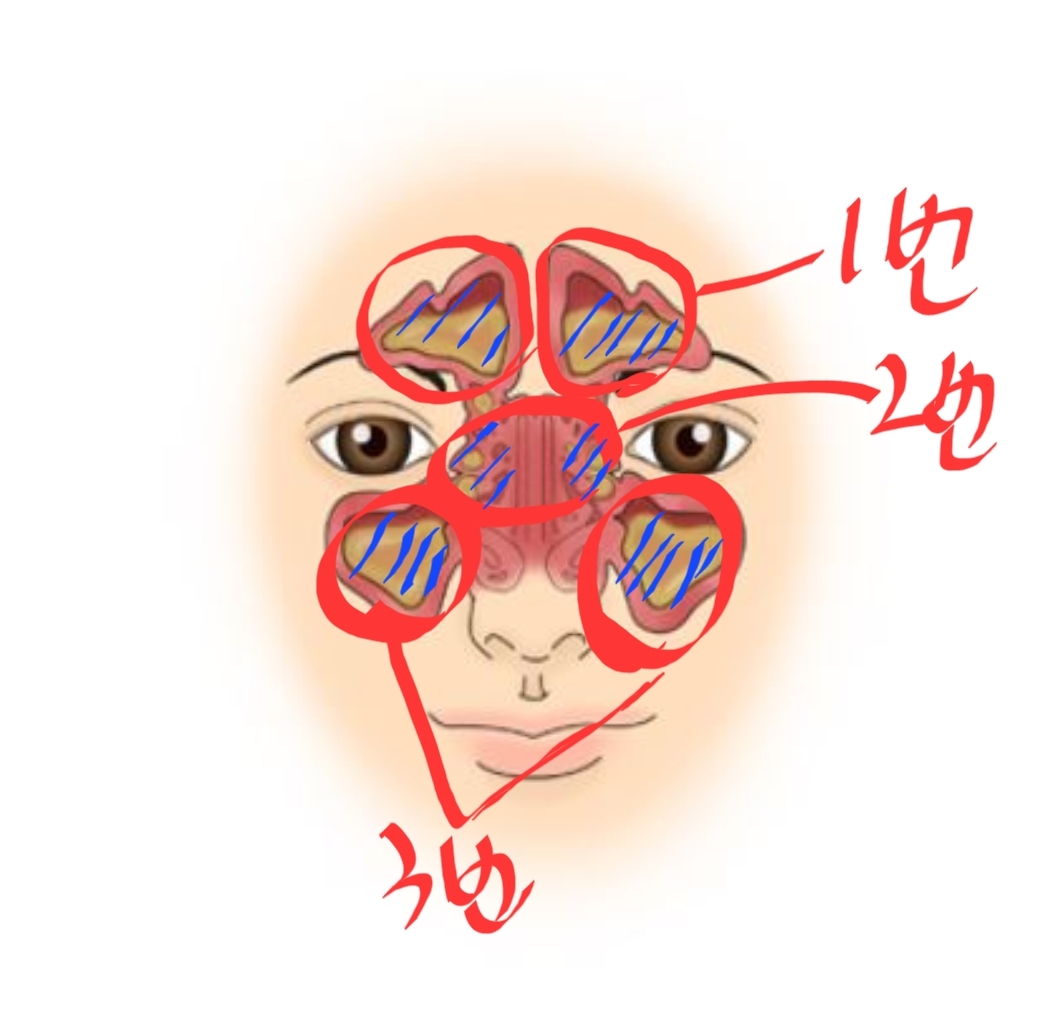

▶ 위 사진 분석

1) 첫 번째 사진: 코 옆 빨간색 동그라미 친 부분

-> 빨간색으로 표시한 부분이 있지요? 첫 번째 사진 보시면 코 옆쪽에 검은색 부분이 있는데 이곳이 바로 부비동입니다. 고름이 차 있으면 저 검정색 부분이 회색으로 보입니다.

2) 두 번쨰 사진: 이마쪽에 빨간색으로 동그라미 친 부분

저 부분도 원래 저렇게 회색으로 채워져 있으면 안됩니다. 검정색으로 보여야 정상안데 저 이마 부분도 검은색 부분이 없는 것으로 보아 고름, 농(염증)으로 꽉 차 있는 것입니다.

그리고 3번 째 말씀드릴 곳은 양쪽 눈 사이 부분인데요, 그것은 아래 사진 보시면 2번으로 적어놓은 부분입니다. 엑스레이 사진에서 눈 사이 부분을 보시면 검은색 부분이 몇 군데 보이는데 저기도 원래 부비동으로 빈 공간이기 때문에 검정색으로 보이는게 정상입니다.

검정색은 농이 차 있지 않고 공간이 뻥 뚫려 있다는 의미에요. 위 엑스레이 사진으로 봐서도 양쪽 눈 과 코 사이 부분도 농으로 차 있는것으로 보입니다.

아래 사진으로 보시면 더 쉽게 이해가 되실겁니다. 1번, 2번, 3번으로 표시하여 설명해 놓았으니 아래 사진과 설명을 천천히 읽어보시기 바랍니다.

위 사진에 이해하기 쉬우시라고 부비동을 크게 1번~3번으로 써 놓았습니다. 이마 위 2곳, 눈과 코 사이 2곳, 양 볼 쪽에 2곳 총 6곳이 엑스레이를 찍었을 때 검은색으로 나타나야(고름이 없고 비어 있어야) 축농증 없는 정상 상태입니다.

제가 엑스레이를 찍었을 때도 공교롭게 위에 올려드린 엑스레이 사진과 비슷했던것 같은데 제가 저는 눈 옆에 농으로 더 꽉 차 있었고 오른쪽 볼쪽에 보이는 검은색 부분도 더 작게 나왔었습니다. 저분보다 제가 더 심했던것 같습니다.

의사선생님께서 특히 눈 옆 쪽에 찬 농을 보시면서 말씀하시기를 제 축농증 케이스가 복잡한 축농증 케이스라고 하셨습니다. 알레르기성 비염이 있어 면역력이 떨어지거나 계절, 온도에 따라 알레르기 반응이 나타나면 바로 재발하는 케이스라고 하셨습니다.